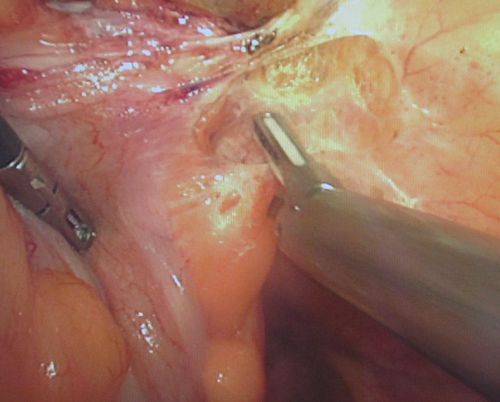

Лапароскопическая нефрэктомия